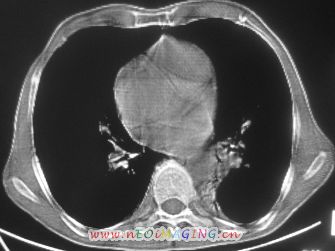

以下是引用卜一在2007-10-7 9:38:00的发言:[br]左下肺胸膜下团片影,内见含气支气管像,临近胸膜未见增厚。多考虑:1 左下肺炎症,建议消炎后复查!2 不除外肺隔离症合并感染!